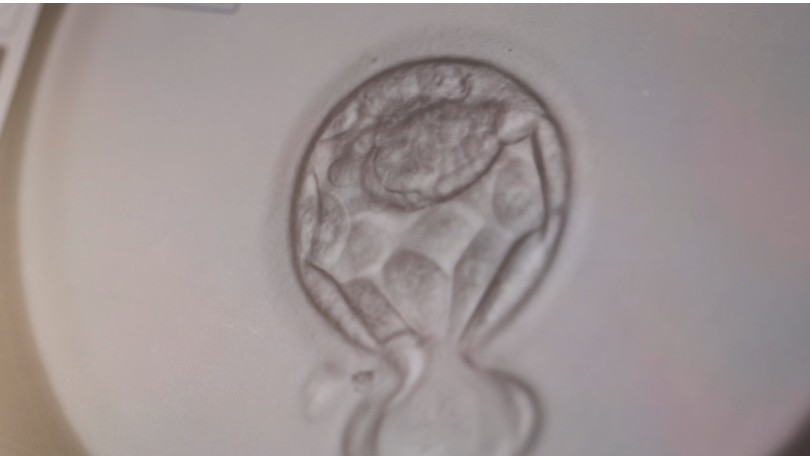

Preimplantation genetic testing (PGT) is a laboratory procedure used during IVF to analyse embryos for specific genetic or chromosomal conditions before they are transferred to the uterus. This testing is performed on a small number of cells taken from the outer layer of a developing embryo, usually at the blastocyst stage (day 5–6).

PGT is performed as part of the IVF laboratory process. After fertilisation, embryos are cultured in the laboratory until they reach the blastocyst stage. At this point:

1. A small sample of cells is carefully removed from the embryo (biopsy)

2. The embryo is usually frozen while testing is performed

3. The sample is analysed in a specialised genetics laboratory

4. Results are returned to help guide embryo selection

This process allows embryologists and clinicians to combine embryo development data with genetic information when planning treatment.